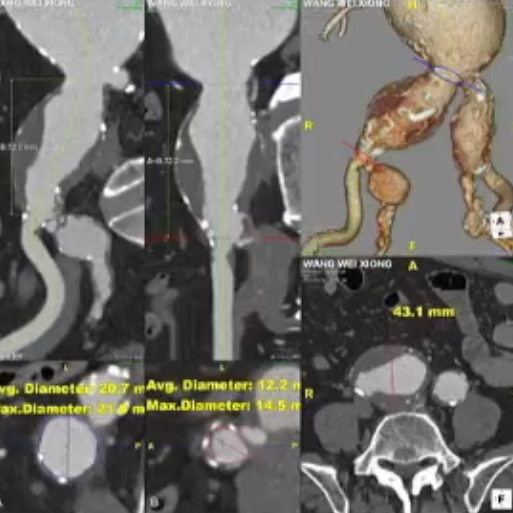

术前情况:78岁男性,腹主动脉瘤和髂动脉瘤,同时右髂总动脉近端、远端严重狭窄且近端扭曲,左髂总动脉近端、远端狭窄,髂内开口狭窄。

手术过程:采用短主体翻山技术重建右侧,在输送主体前,针对髂动脉多处狭窄、扭曲的情况,使用球囊预扩。之后,在微导丝、微导管的配合下艰难超选髂内动脉,成功将支架置入。

术后情况:造影显示患者髂内动脉血流恢复正常,手术达到预期效果。